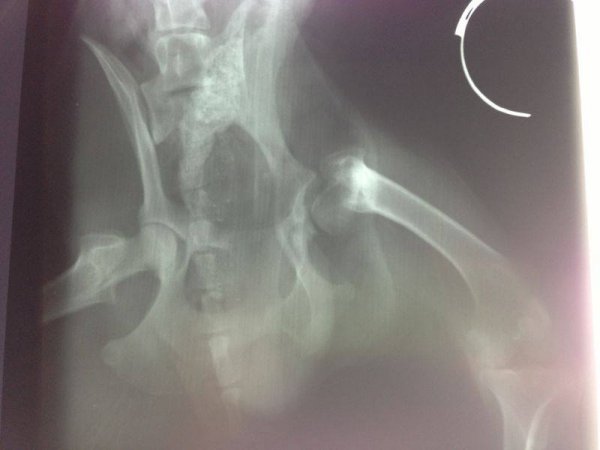

Azul wurde nun in Leon dem Tierarzt vorgestellt, es wurde eine Röntgenaufnahme von seinem Hüftgelenk erstellt, die zeigt, dass eine alte, schlecht verheilte Fraktur den Rüden belastet.

Es ist noch nicht ganz klar, ob Azul eine Hüftgelenksporthese braucht oder ob er mit nicht invasiven Therapien zu einem zufriedenstellenden Ergebnis und guter Lebensqualität kommen kann, darüber werden wir weiter berichten.

Azul bekommt derzeit entzündungshemmende Schmerzmittel, der Tierarzt ist von einer Operation nicht überzeugt und es wird erstmal abgewartet, wie sich sein Zustand nach dieser Therapie entwickelt, danach wird langsam das Schmerzmittel reduziert und darauf geachtet ob Azul weiterhin beschwerdefrei bleibt.